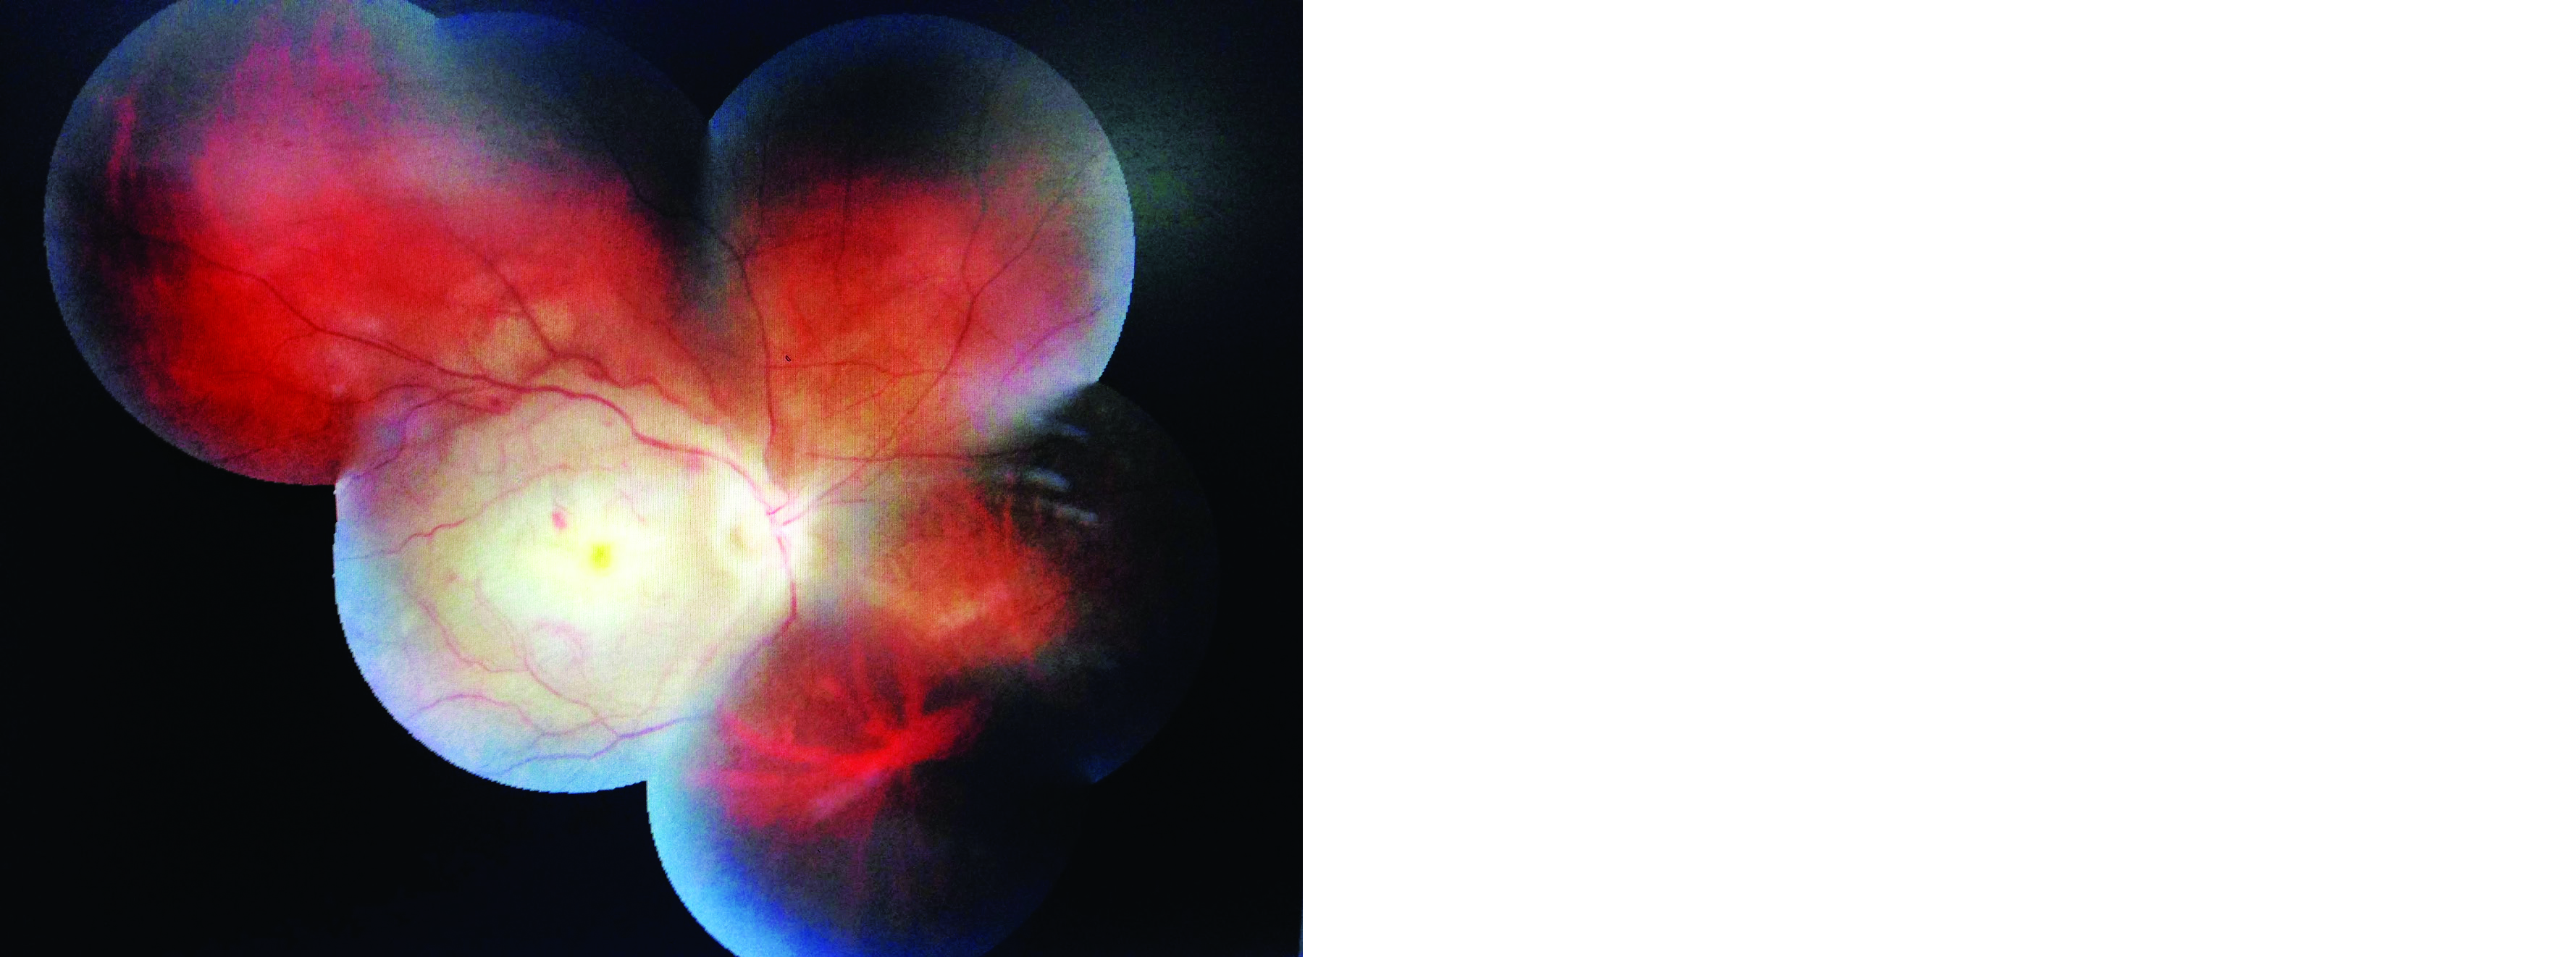

A 34-years-old male presented to us with a history of sudden painless loss of vision of right eye of 6 days duration. The loss of vision was also associated with headache of duration of 6 days. There was no history of trauma, systemic illness. Patient also gives history of alcohol intake twice or thrice a week (120-160 ml each time). Patient was also a smoker. Patient’s visual acuity at presentation was OD No PL OS was 6/6 with presence of relative afferent pupillary defect (RAPD) in OD. Rest of the anterior segment examination was normal. Fundus examination OD revealed optic disc odema and pallor with cherry red spot at the macula and a pale posterior pole with arterial attenuation and superficial haemorrhages in periphery. Extraocular moments were normal (Figure 1).

Figure 1: Fundus photo showing central retinal artery occlusion.